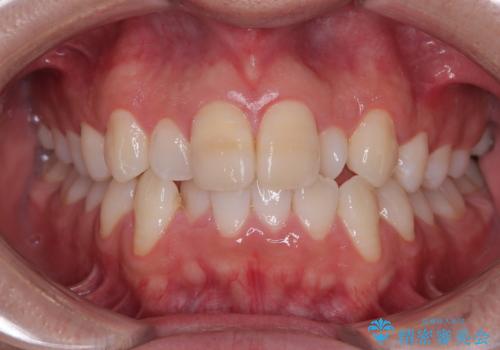

- 「上下の前歯がガタガタしているのが気になる」とのことで来院された患者様です。

上下顎前歯部に叢生(歯の重なり・ガタつき)を認め、見た目だけでなく、歯磨きのしにくさも気にされて来院されました。